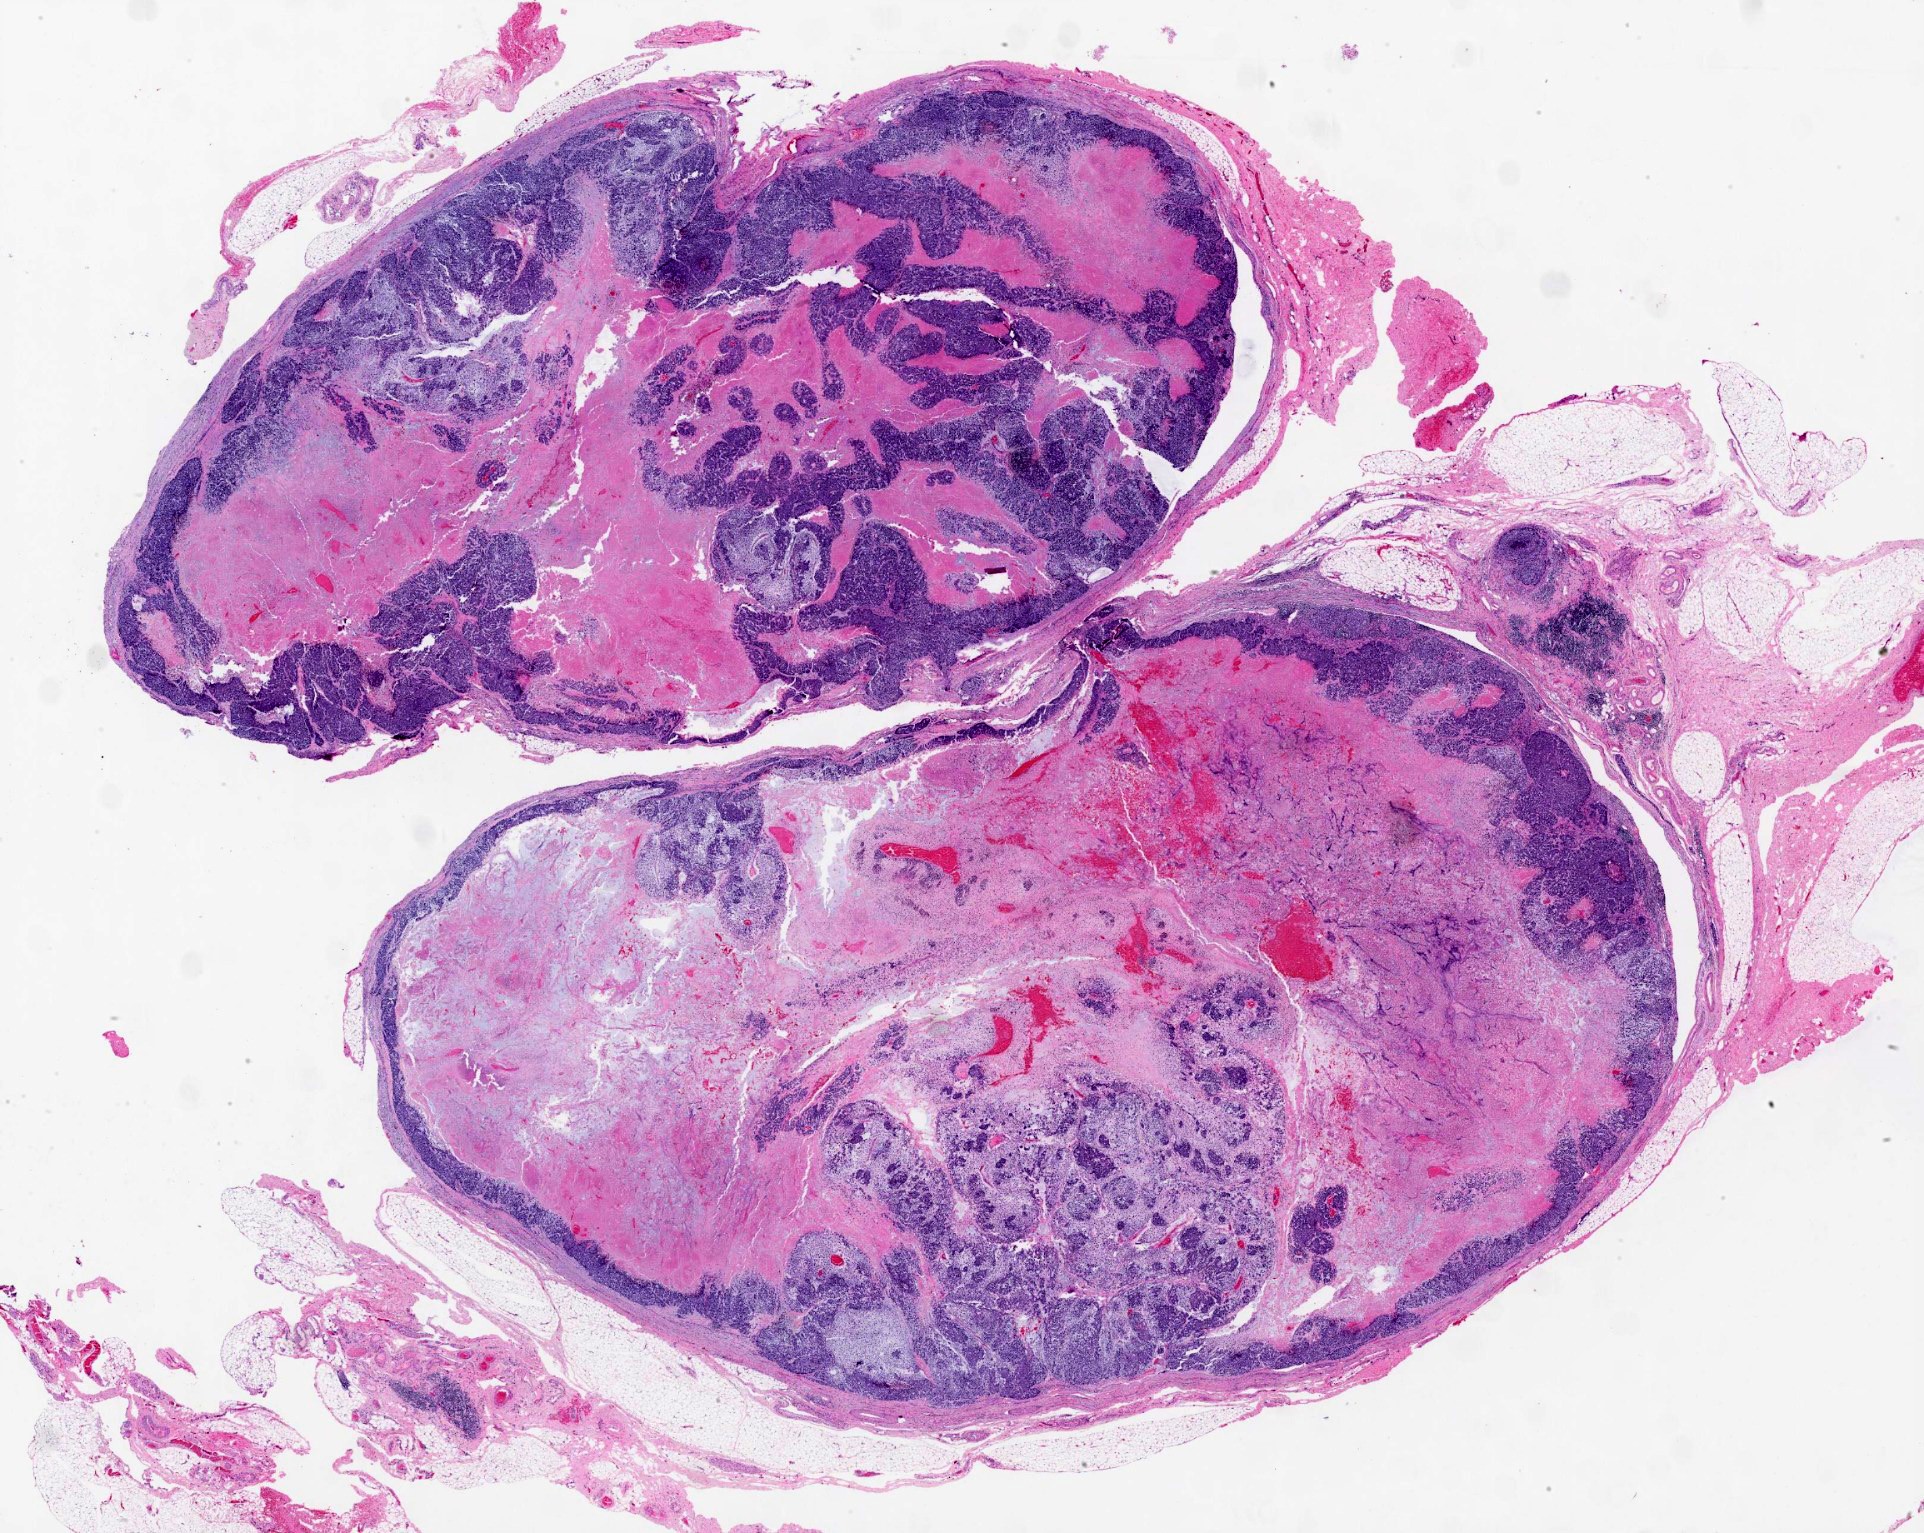

- Invasiveness is typically demonstrated as expansile invasive multinodular growth: myoepithelial carcinoma rarely shows infiltration of single cells / small clusters or desmoplastic reaction

- Nodules often have a hypocellular center with hyalinized stroma or bland necrosis surrounded by a hypercellular peripheral zone

- Tumor necrosis can be seen within the hypercellular central zone of a tumor nodule

- Currently, there is no well defined, widely accepted grading system: presence of tumor necrosis is considered by some as a feature of high grade myoepithelial carcinoma (Am J Surg Pathol 2015;39:931)

- Common architectural patterns include solid, trabeculae, cords, nests and single cells

- Presence of pre-existing / residual pleomorphic adenoma component can be seen in myoepithelial carcinoma ex PA

Contributed by Abeer Salama, M.D. and Bin Xu, M.D., Ph.D.